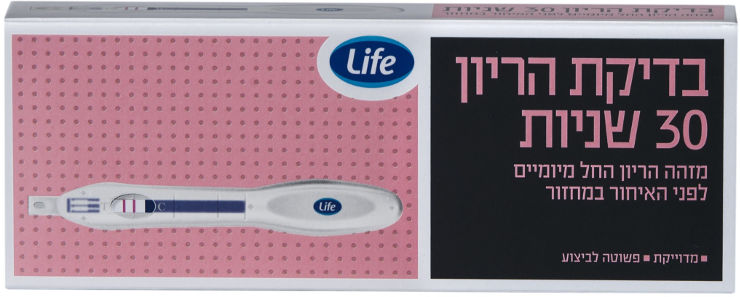

- בדיקת הריון 30 שניות

בדיקה עצמית להריון בעלת רמות רגישות ודיוק גבוהות ביותר המאפשרות שימוש בשלב מוקדם מאד של ההריון.

ברקוד מוצר: 7290103434250

ערכה כוללת: הוראות שימוש, מקלון בדיקה עם שקית קטנה המכילה חומר מייבש להגנת הבדיקה מלחות ועד לביצועה. מתאים ל: ניתן להשתמש החל מיומיים לפני האיחור במחזור. תכולה: 1 ערכהבתהליך ההזמנה ניתן לבחור לאסוף מסניף סופר-פארם לבחירתך או משלוח לכתובת מבוקשת. מדיניות המשלוחים של האתר מפורטת במדיניות המשלוחים החזרות והחלפות: כל מוצר שנרכש ברשת סופר-פארם, בחנות ו/או באתר (לא כולל מוצרי מוכר חיצוני), ניתן להחליף/להחזיר בכל סניף כנגד חשבונית קנייה ובכפוף למדיניות ההחזרות שברשת.